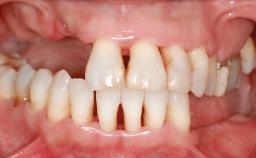

Ridge Preservation and Implant Placement for a Fixed Dental Prosthesis After a Car Accident

It is well known to clinicians that any removal of teeth will, over time, cause the dimensions of the alveolar ridge to be reduced by resorption of the bundle bone and by changes related to external modeling. This development is particularly evident in the crestal region with its thin buccal bone that consists of bundle bone almost entirely. The facial bone will rapidly resorb as blood supply from the periodontal ligament gets disrupted (Araújo and Lindhe 2005). There is no reason why traumatic tooth loss should not have the same consequences. It takes more than achieving implant osseointegration for a treatment outcome to be considered successful. No deficiency of bone or soft tissue is acceptable when an ideal esthetic outcome is the goal. Several articles (Sanz and coworkers 2011; Vignoletti and coworkers 2011) have reported on techniques of improving the alveolar ridge for implant treatment, notably focusing on protecting tissues from resorption.

# of Teeth 6

Width of Edentulous Span 1 tooth (>= 7 mm) 1 tooth (< 7 mm) 2 teeth or more

Bone Volume Horizontally and vertically sufficient Horizontally deficient Deficient vertically or deficient vertically AND horizontally